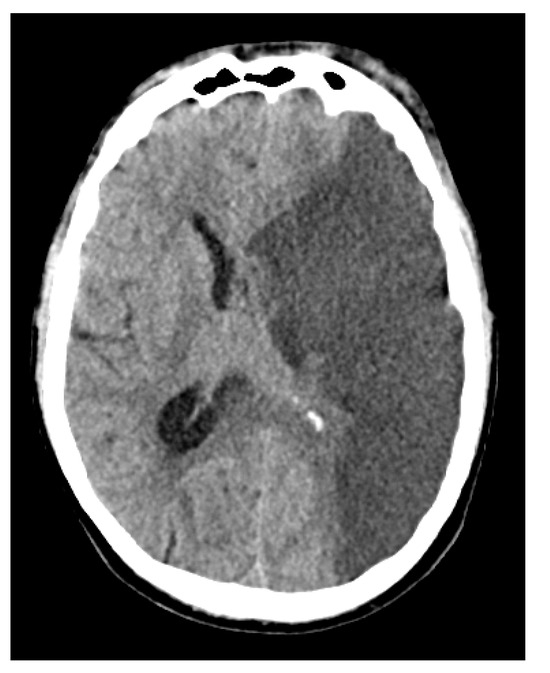

Clinically, the patient’s condition remained poor despite all interventions. A surgical intervention was planned in collaboration with the ENT and ophthalmology teams. However, during preoperative imaging (Figure 7), a malignant MCA infarction with significant midline shift of approximately 1 cm was revealed corresponding to a newly demarcated infarction across the entire left MCA territory. Given the severity of these findings and in alignment with the presumed wishes of the patient, a decision was made to shift the focus of care to palliative treatment. The patient died 12 days after initial presentation and 16 days after symptom onset.

Figure 7.

Non-contrast CT scan of the head demonstrating a hypodense area in the left middle cerebral artery territory, indicative of malignant media infarction. The left lateral ventricle is partially compressed, and there is a midline shift of 1–2 cm to the right, suggesting mass effect due to the infarction. No hemorrhagic transformation is seen.